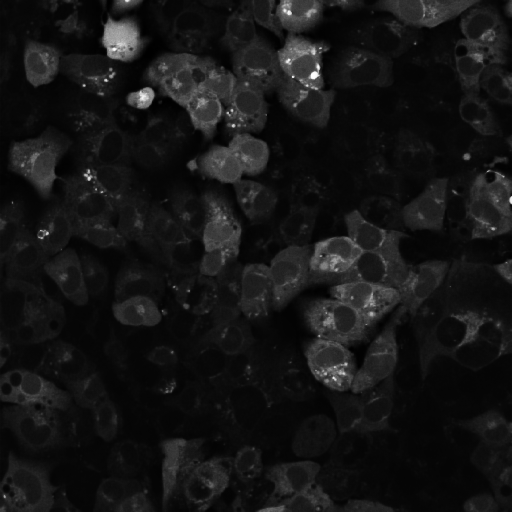

6.2 GT comparison

Samples of images generated using our pipeline were shown to an expert experimentalist for the selection of preprocessing-projection method combinations which could provide comprehensive, useful and different information about the cardiac cell networks imaged for GT annotation. Selected methods are shown in Figure 6. GT annotations generated using the selected projections were compared with annotations generated from composite grayscale images obtained using conventional frames stacking and averaging methods [7]. Due to visualisation constraints in old composite images due to low brightness and impaired image quality, only 77 images were analysed at this stage. New GT () and old GT () annotations were compared using two levels of analysis:

As illustrated in Table 3, we observed notable variance in IoU scores across the dataset. To better understand this variability, we visually examined three representative cases from and , one with the lowest IoU (Figure 6(a) and (d)), one with the highest (Figure 6(c) and (f)), and one approximating the metric’s median (Figure 6(b) and (e)). Our analysis revealed that images taken at higher microscope magnifications (Figure 6(c) and (f)) yielded higher IoU scores between and , indicating alignment between the two GTs. This suggests that increased resolution may facilitate consistent segmentation.

Furthermore, in these high-magnification cases, provided clearer delineation of cellular boundaries and background regions, particularly at the image corners, where segmentation is typically more challenging. In the lowest IoU examples (Figure 6(a) & (d)), revealed more complete cell structures and extended boundaries, indicating improved visibility and segmentation accuracy.

Additionally, BG , which highlights instances where regions previously labelled as cells in were reclassified as background in , was found to be higher than BG , suggesting that noise reduction or enhanced visibility improved the accurate delineation of true cell regions in .

One of the key requirements for efficient image fusion is that the fused image must preserve all the quantitative information contained within the original video recording and contain more detailed information about the scene or object depicted than the isolated frames alone. Cell-level comparison of CA and CC in GTo and GTn annotations proved that images generated through the image fusion method presented in this study contain a higher number of cells, averaging a increase in cell count (from a median of 52 cells identified in to a median of 75 cells in ), than images generated using conventional frames stacking and averaging methods (Table 3 and Figure 2b). These results suggest two main things: 1) our pipeline is more effective than previously employed methods [7] at combining data from multiple frames while reducing temporal inconsistencies across frames caused by fluctuating fluorescence signal intensity within cells. Therefore, projected images generally retain more complete information about the cellular network for downstream annotation (Figure 8); 2) efficient noise removal and contrast enhancement by our proposed approach improves the visibility of cellular boundaries, facilitating the separation of individual cells within dense and overlapping cellular regions characterised by cellular aggregation (Figure 7). This last assumption is further corroborated by the results achieved from the analysis of pixel-level agreement between GTo and GTn. By comparing BG and BG (Table 3), is therefore evident that a higher percentage of pixels identified as cells in GTo were changed to background pixels in GTn than vice-versa. This shift suggests that noise was either removed by our projection pipeline or that improved visibility and image sharpness, especially around cellular boundaries, enabled more accurate identification of true cell regions. Therefore, as shown in Figure 7a and 7d, large cells in were often segmented into multiple smaller cells in , likely due to enhanced boundary detection. This is also suggested by the lower CA and higher cellular density recorded in than (Figure 8), where the lower amount of larger cells recorded in suggests the under-segmentation of low-brightness cellular regions with unclear boundaries from unprocessed composite grayscale images. Overall, these observations support the hypothesis that the revised preprocessing pipeline produces more precise and biologically consistent segmentations.